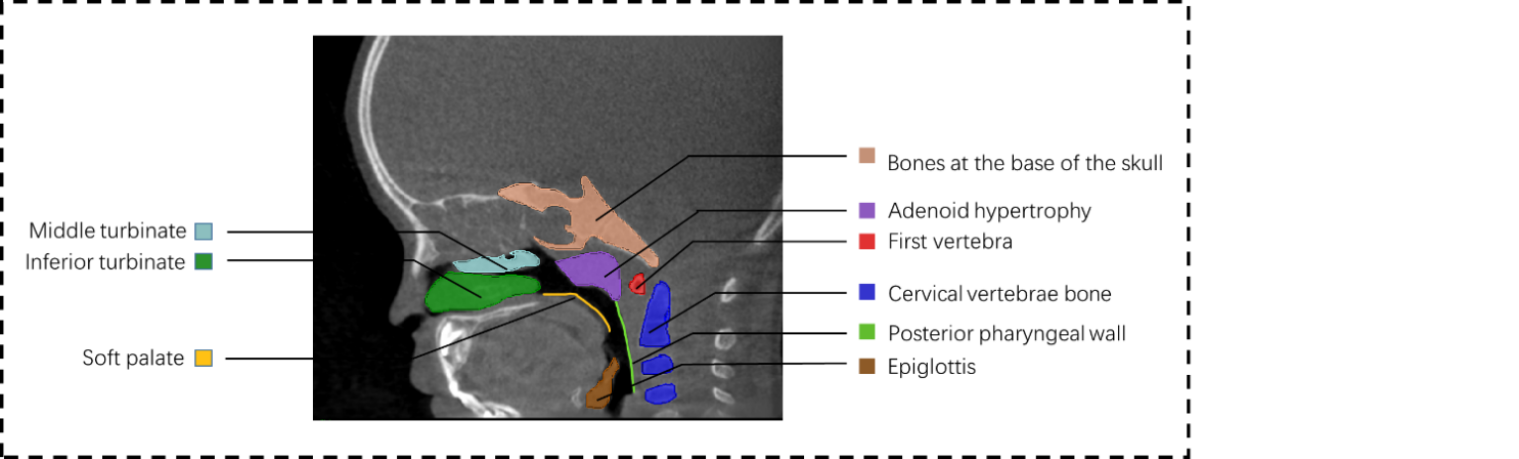

Subsequently, through CT images, a broader physiological context is accessible, as illustrated in Fig. 1, encompassing structures such as the skull, vertebrae, soft palate, epiglottis, and turbinates. The specific target for segmentation is denoted in purple, representing the hypertrophied segment of the adenoids. CT reveals that the hypertrophied portion is located within a confined airway space, surrounded by numerous bones, muscles, and fascial tissues, necessitating careful consideration during surgical interventions. Surgeons traditionally rely on nasal endoscopy [7] and oral endoscopy [8] for visualizing this intricate anatomy. However, nasal and oral endoscopy provide only a two-dimensional perspective with a limited field of view, presenting challenges during surgery. Consequently, physicians increasingly seek computer-assisted pre-segmentation and planning for adenoid surgery to alleviate the procedural burden. Consequently, the application of deep learning for analyzing adenoid hypertrophy in the nasopharynx is gaining popularity. Notably, there is currently a gap in the literature concerning deep learning-based segmentation specifically tailored for adenoid hypertrophy in CT scans.

Refer to caption

Figure 1: Schematic representation of tissue structures in CT of the head.